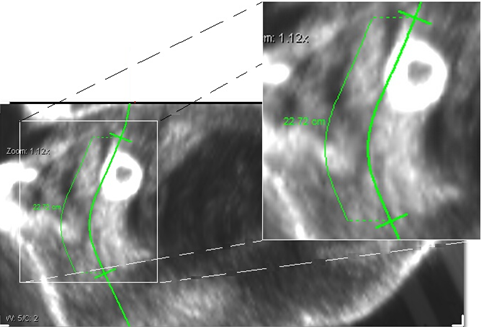

It is possible to find the distance between two reference points in the curved MPR by selecting the Display Curved MPR image option and then pressing Ctrl+Double-Click + left mouse button to find the distance between two specific reference points on the curved MPR.

There is a four step process which requires the following actions:

- Create a path by selecting the option Create Path.

- After the path has been created, click on Display Curved MPR image.

- Once the path has been created, press Ctrl+Double-Click the left mouse button to create a first reference point for measurement.

- Press Ctrl+Double-Click + left mouse button again to create a second reference point for the measurement.

The distance between the reference points will be displayed in centimeters. You can change the reference points by sliding them up or down the path and create further reference points to view distances between them.